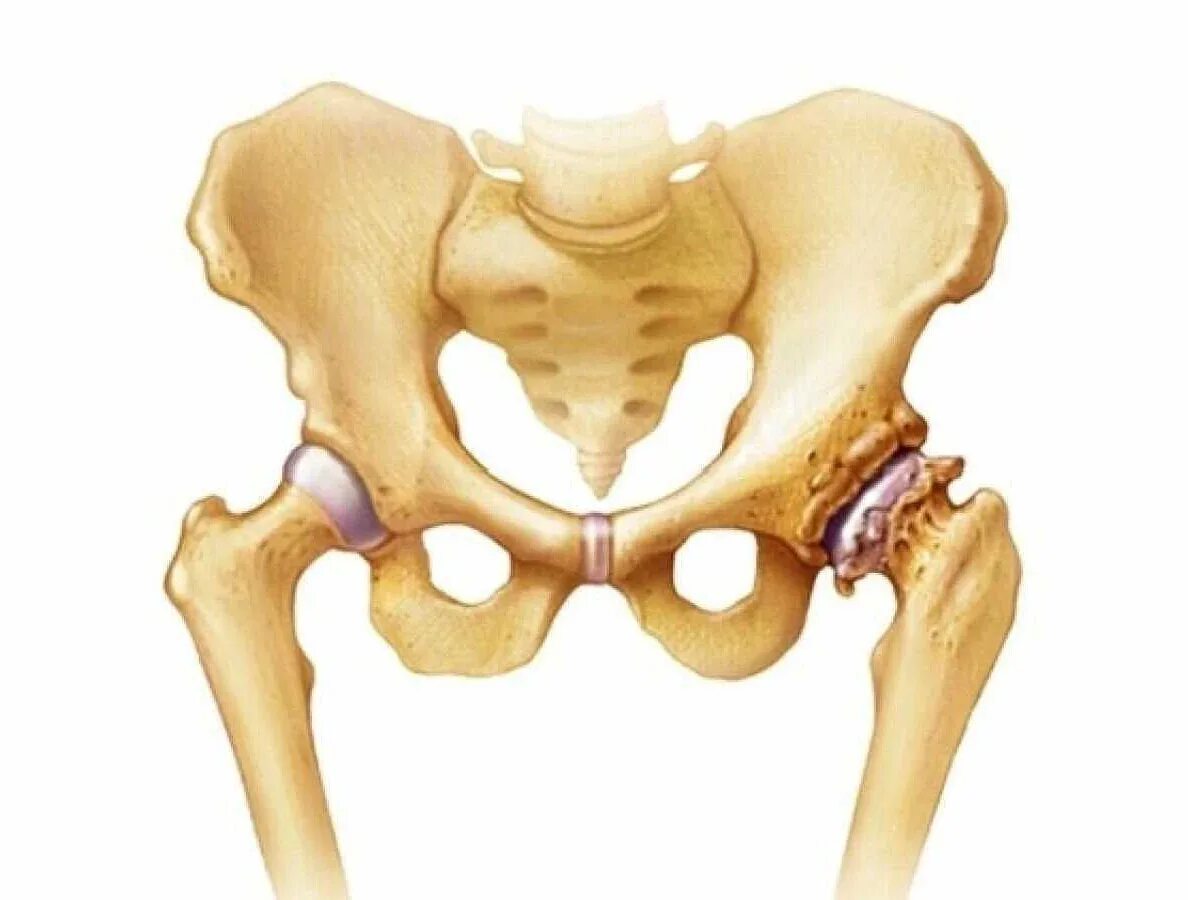

Артроз тазобедренных суставов 1 стадии